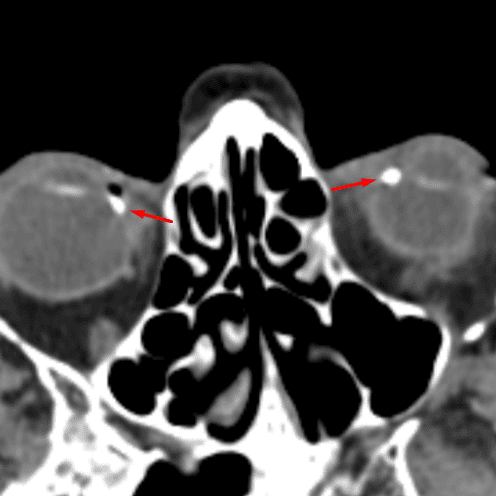

Optic Disc Drusen

Case 14

Free